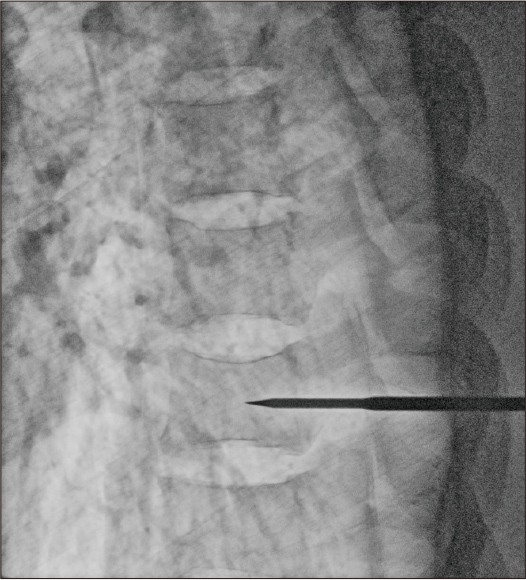

Dosis: 4,2 mA

Nach Anwendung der dynamischen Verarbeitung + Rauschunterdrückung